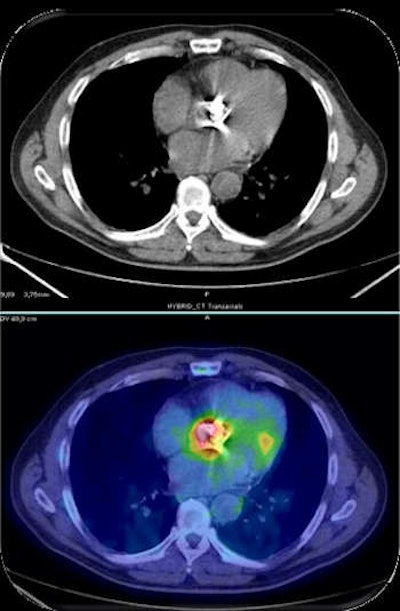

FDG-PET/CT scan of a human patient shows prosthetic valve endocarditis.What will be the central themes at your annual congress in Milan?